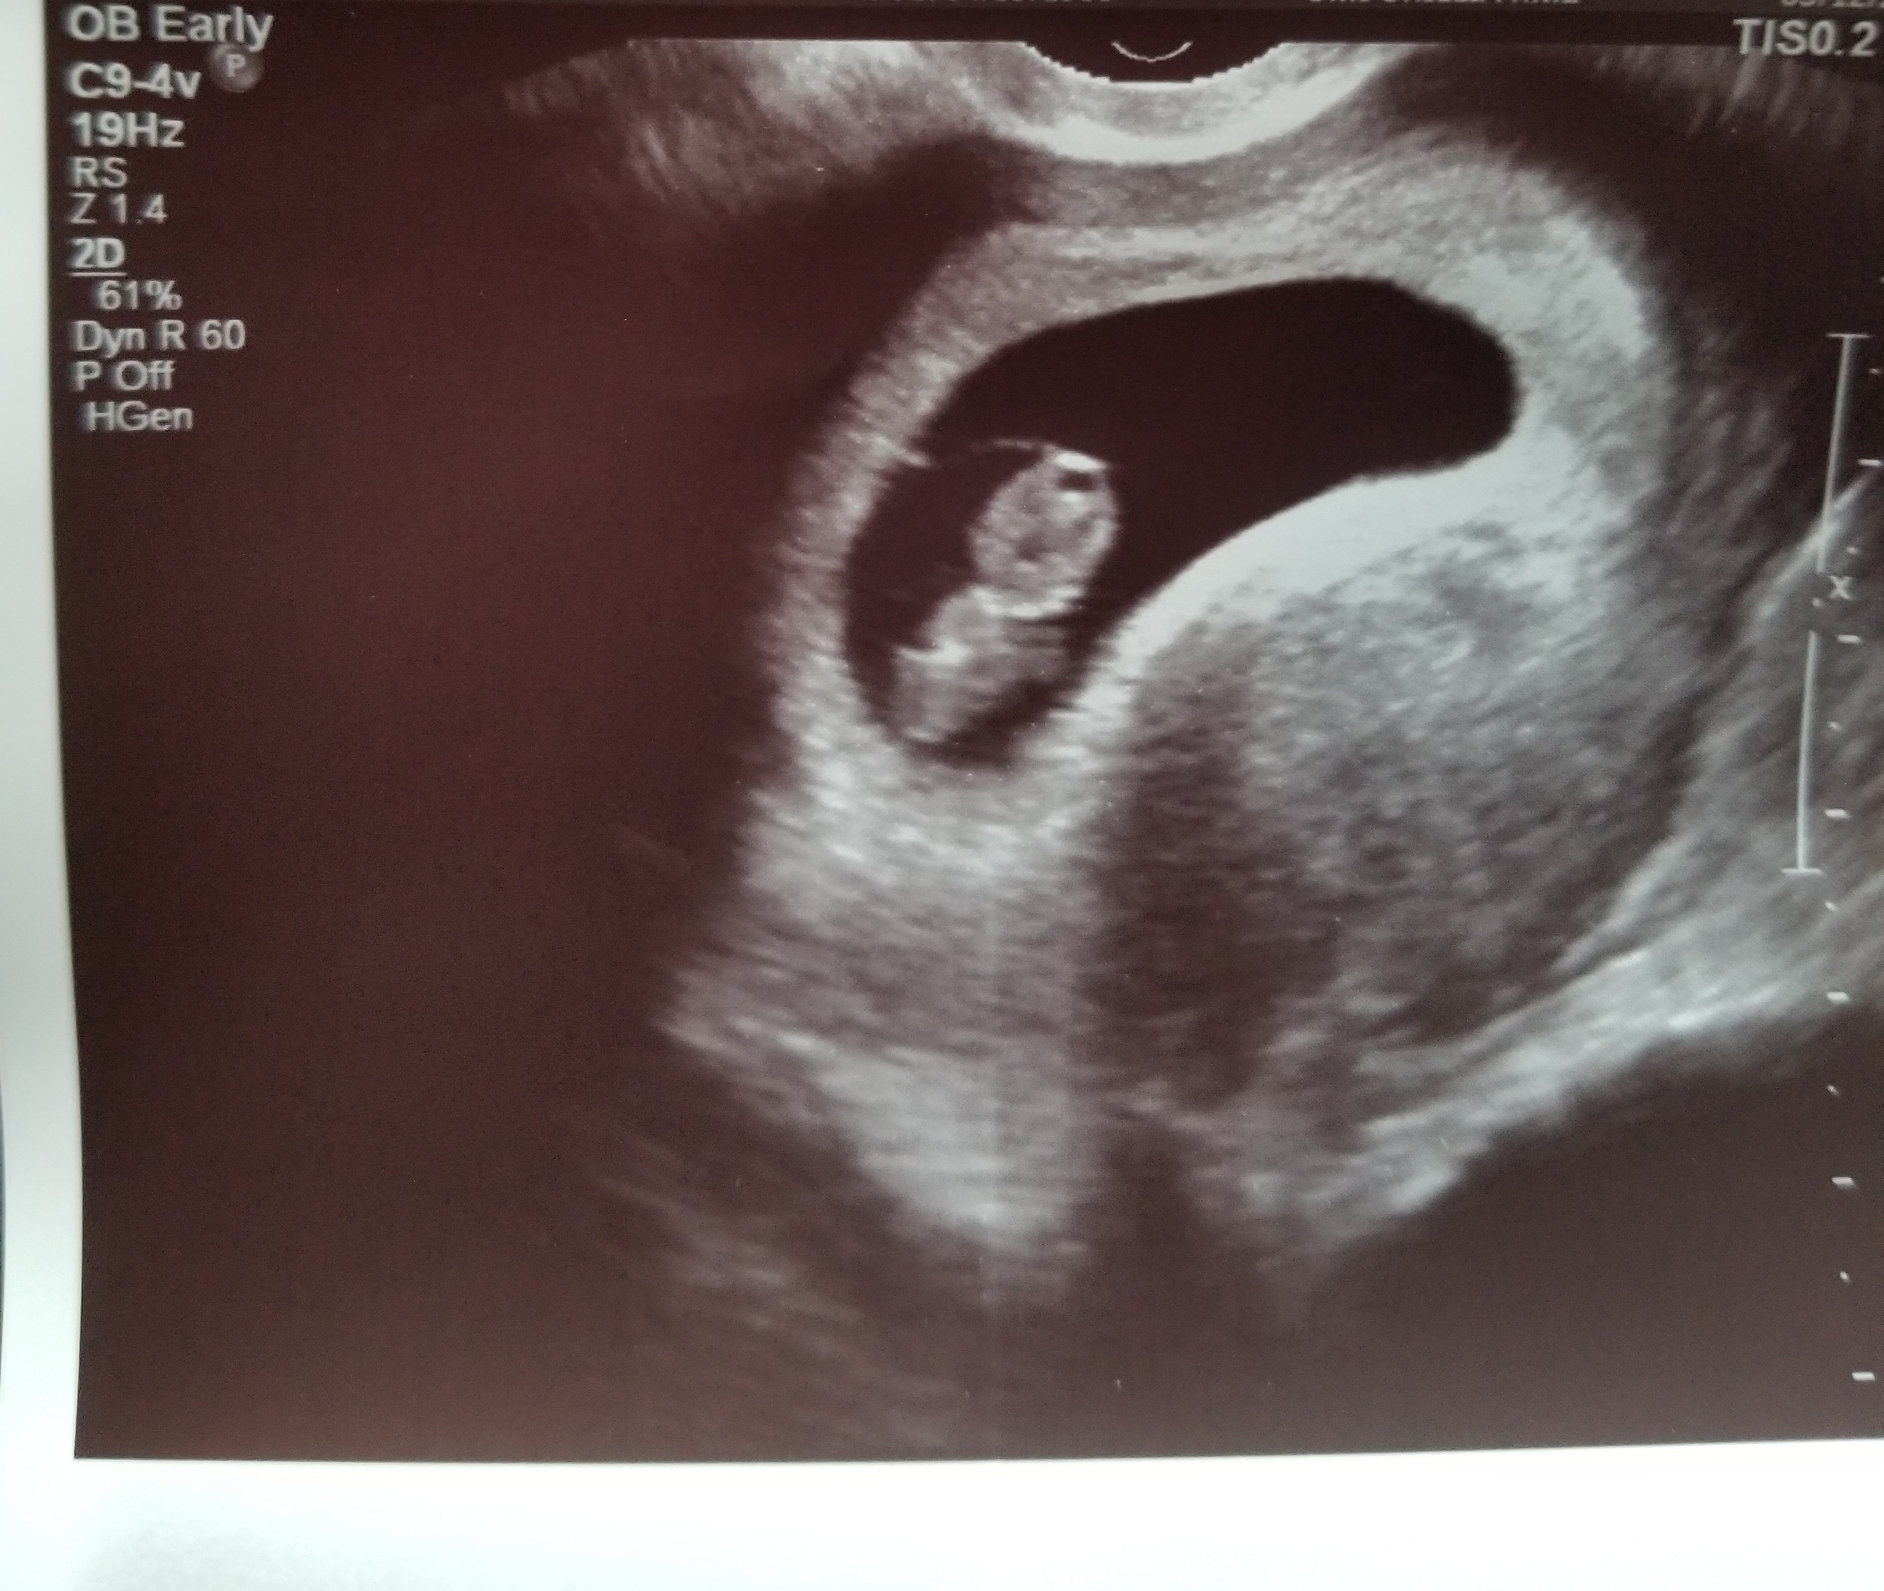

Hi everyone! My EDD is 7/1/2019, so I’m not sure if I’ll be here or in June. Here is our ultrasound photo from 8 weeks (transvaginal) a couple weeks ago. Heartbeat was 172bpm. Baby is the blob on the upper right, facing away.

Here is our ultrasound photo from 8 weeks (transvaginal) a couple weeks ago. Heartbeat was 172bpm. Baby is the blob on the upper right, facing away.